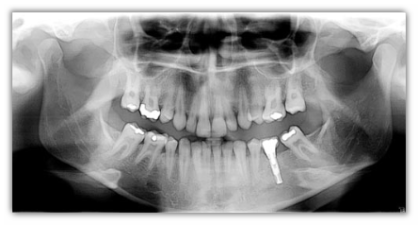

Trophy Radiologie panoramico digitale TrophyPan

TrophyPan

L'ortopantomografo totalmente digitale.

TrophyPan e completamente ed esclusivamente digitale e risulta l'espressione di tutti i vantaggi offerti da questa tecnologia. L'immagine viene trasmessa al personal computer in tempo reale durante la rotazione della testa e si completa in circa 15 secondi, senza tempi di attesa e senza tutti i problemi relativi allo sviluppo.